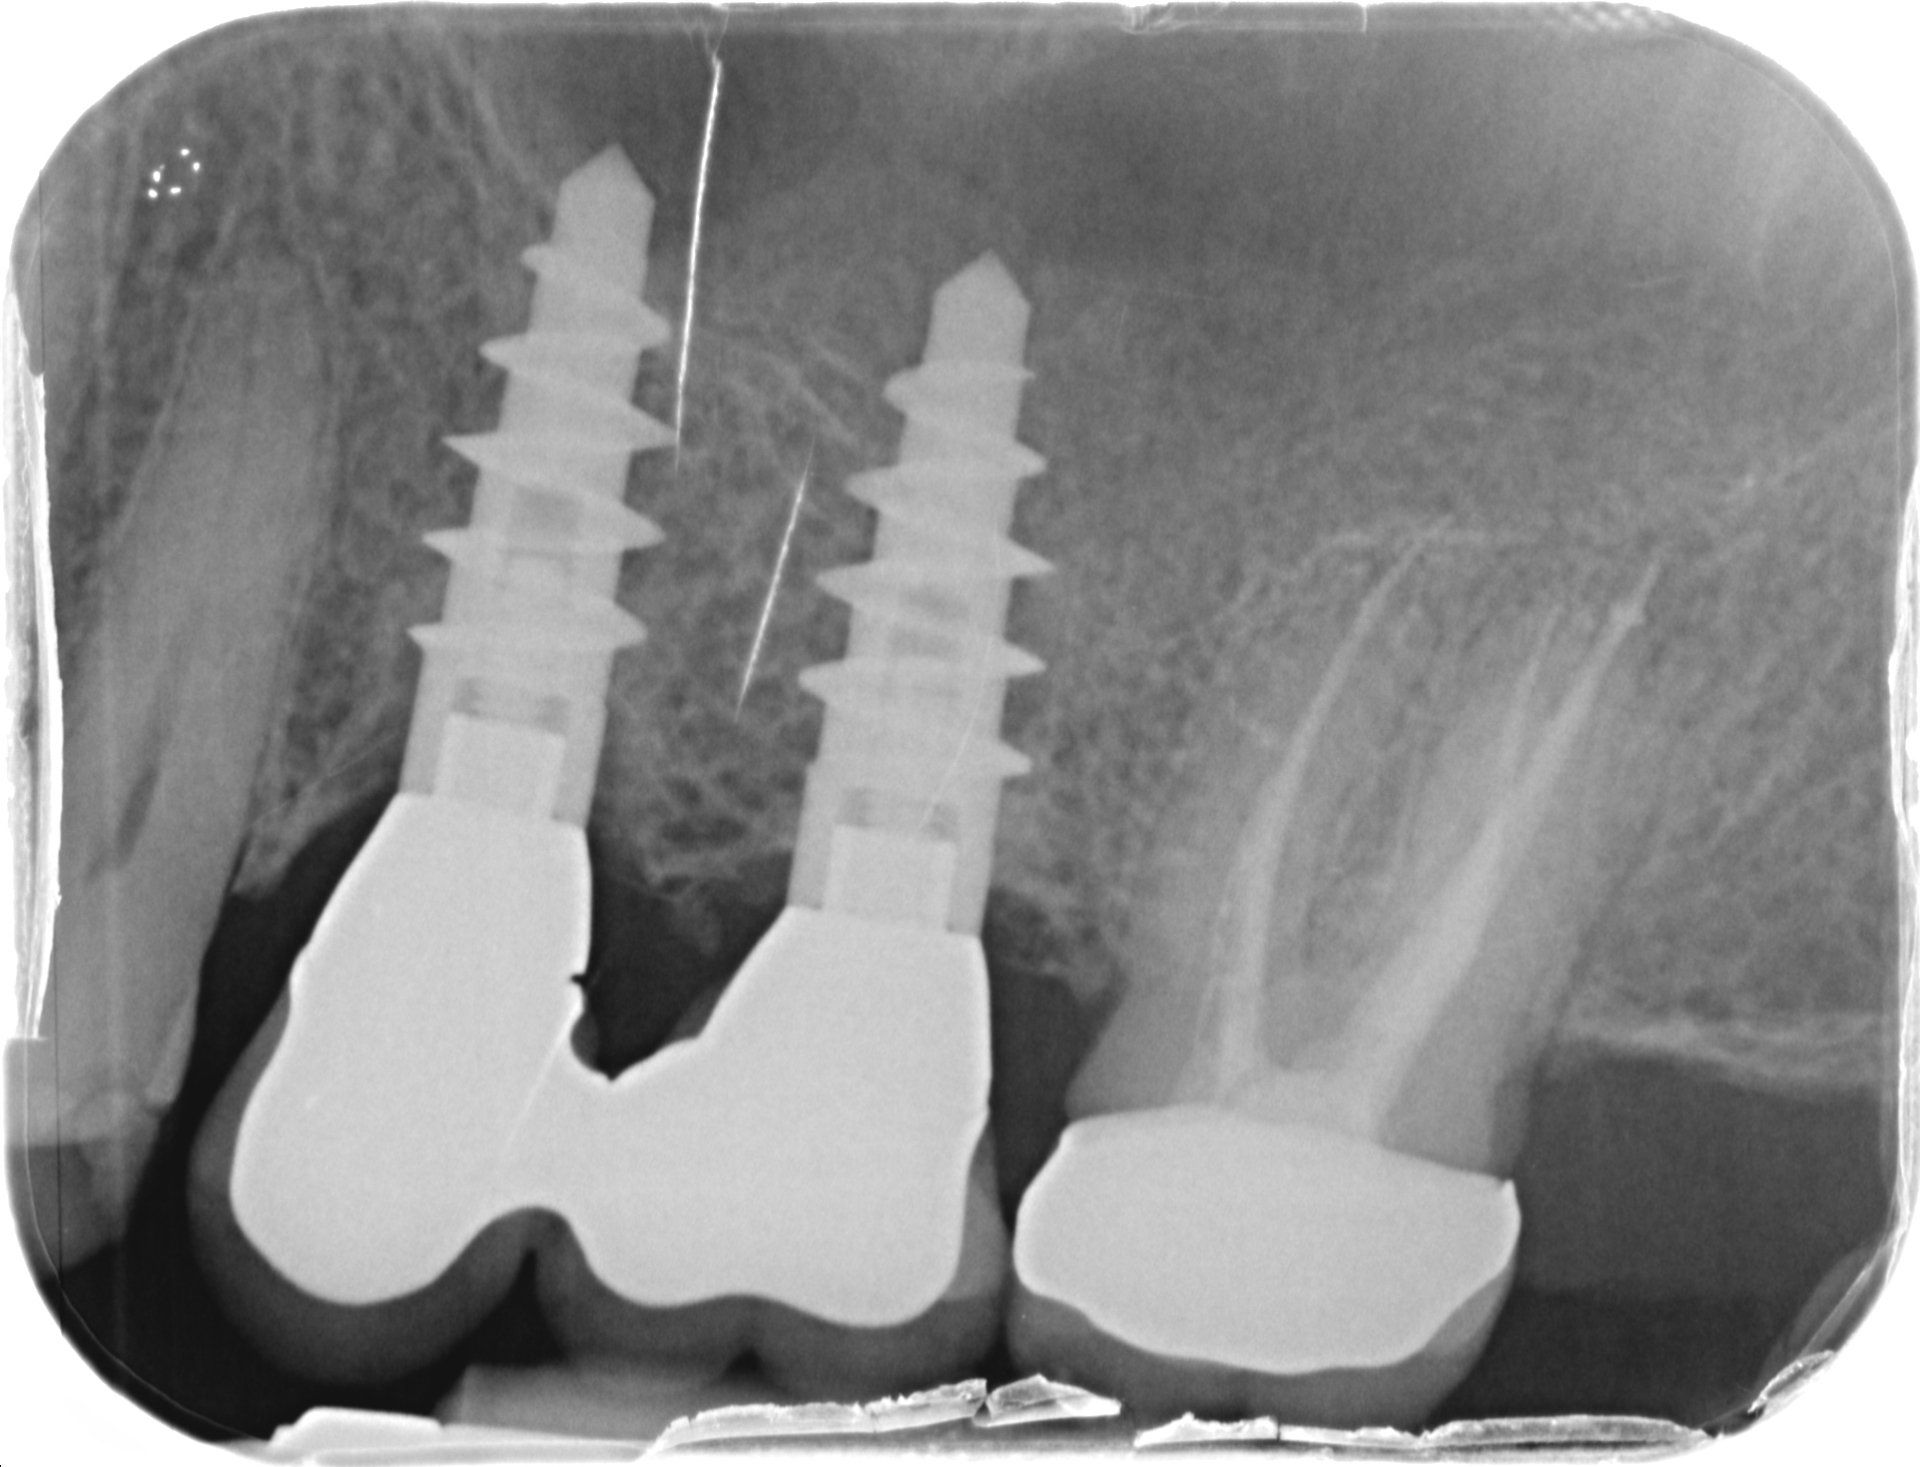

Il paziente di questo case-report è un uomo di 52 anni, che non presenta patologie sistemiche, non fuma e non assume farmaci in modo abitudinario. Ha due impianti dentali posizionati dieci anni prima in zona 2.5 e 2.6 (Fig 1) con mucosite.

#dida Fig. 1: Ortopantomografia al baseline

Come evidenziabile dalla cartella parodontale sottostante (Fig. 5) il P.I. corrisponde al 92%, il BoP al 99% con sanguinamento abbondante in zona 2.5 e 2.6 (Fig. 6). L’assenza di perdita di osso radiografica è stata confermata dalla radiografia endorale (Fig. 7).

#dida Fig.7: Radiografia endorale a T0